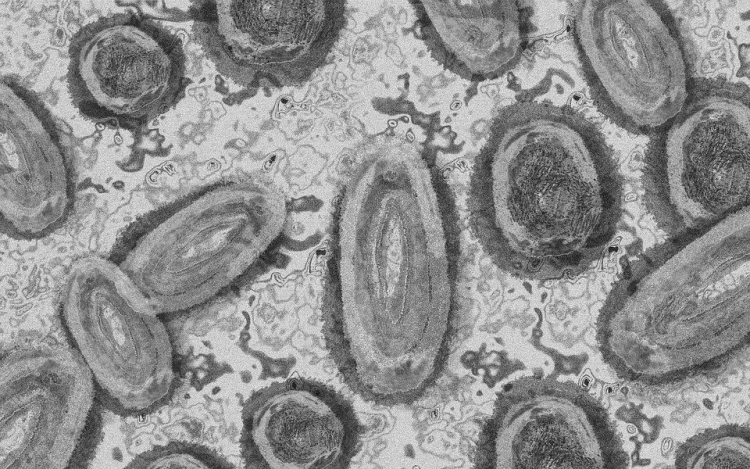

Forrás: mti/illusztráció: pixabay

Megfertőződött majomhimlővel egy négyéves kislány Németországban - jelentették kedden német hírportálok az országos közegészségügyi intézet (RKI) adatai alapján.

Németországban első alkalommal mutatták ki a kórokozót gyermek szervezetében.

A kislány két fertőzött felnőttel él együtt a Baden-Württemberg tartományi Pforzheimben. A tartományi egészségügyi minisztérium tájékoztatása szerint elővigyázatosságból vizsgálták meg, miután kimutatták az első fertőzést a háztartásban. Eddig nem jelentkeztek nála a betegség tünetei.

Az RKI-nál május elején regisztrálták az első németországi majomhimlős eseteket. Keddig 2982 igazolt fertőződést jegyeztek fel. A betegség mind a 16 tartományban megjelent.

Az intézet ismeretei szerint a vírus elsősorban szexuális úton terjed Németországban, főleg férfiak körében. A fertőzöttek szinte mind felnőtt férfiak, csupán hét nő és két kiskorú - egy 15 és egy 17 éves kamasz - van közöttük.

Az esetek többségében a fertőzés enyhe lefolyású betegséggel jár. Halálos áldozatot Németországban még nem regisztráltak.

Az Afrika egyes részein évtizedek óta ismert és ritkán előforduló majomhimlő május óta Európában, Észak-Afrikában és más térségekben is terjed. Az Egészségügyi Világszervezet (WHO) júliusban globális egészségügyi vészhelyzetnek nyilvánította a járványt.